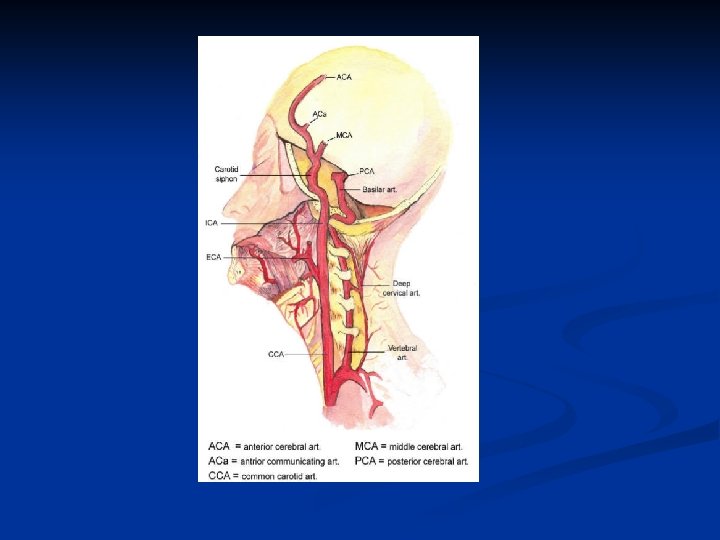

Anatomy n Aortic Arch n Innominate or Brachiocephalic artery n Right subclavian artery n Right common carotid Left common carotid artery n Left subclavian artery n n CCAs lie posterolateral to thyroid n Deep to sternocleidomastoid muscle n

Anatomy Right CCA originates from innominate artery n Left CCA originates from aortic arch n CCAs divide into ECA and ICA n ICA has no branching vessels in the neck; may have slight dilation just past its origin; supplies face and head; lies posterior in the neck n ECA has branching vessels; usually smaller than ICA n n Vertebral Arteries – lie between transverse

ICA n n n n The internal carotid artery supplies the brain, the eye, the forehead, and part of the nose. It enters the cranial cavity via the carotid canal in the temporal bone. It gives off no branches within the neck region. The internal carotid artery supplies perfusion to the anterior and middle portion of the brain, the eye and its appendages and sends branches off to the forehead and nose. It originates at the carotid bifurcation and courses, via a number of curvatures, through the base of the skull into the Circle of Willis. The proximal-most portion of this vessel is rather bad bulbous and is referred to as the bulb. Distal to the bulb, the artery narrows and is referred to as the ICA proper. Anatomically, the ICA is distinct from the ECA in that there are no branches until it passes through the base of the skull. After coursing anteriorly to the transverse processes of the first three cervical vertebrae (C 1 –C 3), it enters the carotid canal of the petrous portion of the temporal bone. The intra-petrous portion of the ICA is also referred to as the cavernous portion of the ICA. After coursing through the base of the skull, its first branch arises, the ophthalmic artery, which supplies blood to the retina. (This is of clinical importance when discussing amaurosis fugax). At the base of the brain, the ICA gives rise to the anterior and middle cerebral arteries. The site of this branching is often referred to as the carotid siphon.

Circle of Willis (connecting the two) n n n Major collateral pathway of brain Basilar artery formed from fusion of both vertebrals Internal carotid arteries Anterior cerebral Middle cerebral Basilar artery Posterior cerebral Communicating vessels Anterior communicating artery (acoa) Posterior communicating artery (pcoa)